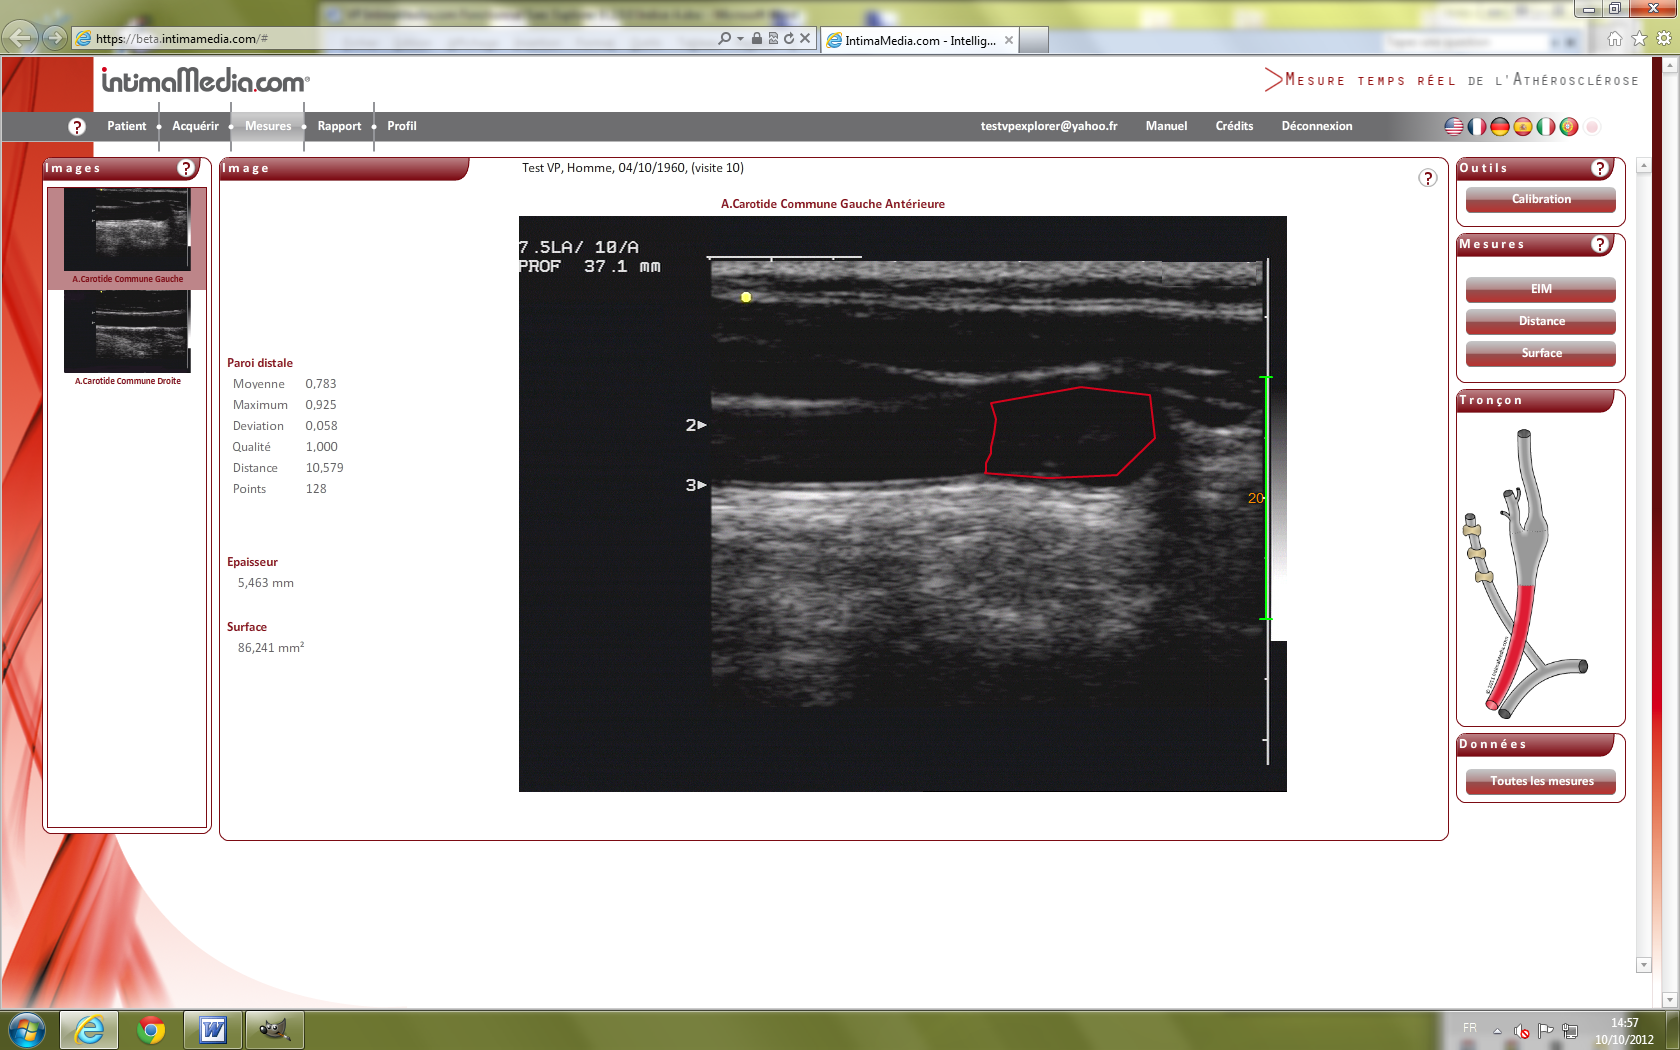

Images VP IExplorer 9. IntimaMedia 2.0.0 Fonctionnal

Test38.png